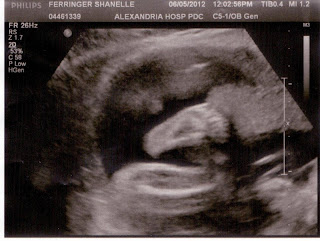

And here's a little face. You can see his eye, then a whitish line. That's his arm. He kept covering his face. I guess he's going to be like Dippy for having his picture taken!